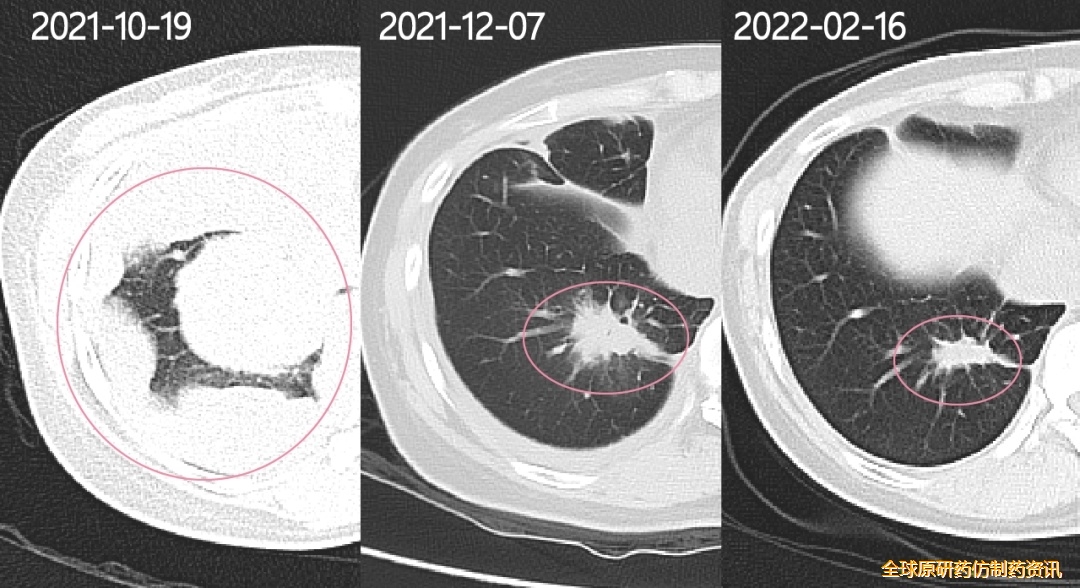

回看老婆每次复查的影像报告,一开始那个5厘米大的肿瘤和一些小瘤子,就像包子一样,鼓鼓囊囊地塞在了老婆的右侧胸腔中,但经过有效治疗后,现在看上去只剩1粒花生米大小了,影像上看胸壁也已经光滑圆润。

5.48CM*5.4CM(确诊时):1.8CM*1.8CM(奥希替尼35天);1.4CM*0.9CM(奥希替尼108天)

2021年12月7日复查

抽了5管子血,但幸运的是带给了我们惊喜!老婆肺部内大的肿物5.48CM*5.4CM缩小到1.8CM*1.8CM,小的病灶开始消失,血液指标也基本正常。

2022年2月17日复查

影像上一切都很好,之前的积液已经全部吸收,整个胸壁轮廓清晰,能看到的只剩下一个肺部病灶,对比了初诊影像(右肺及右胸膜多发恶性占位肺部原发肿瘤5.48CM*5.4CM)和去年12月7日影像(右肺及右胸膜少许结节影原发肿瘤1.8CM*1.8CM),说我们疗效非常好叫我们放宽心不用去担心,即使进展了他们也会有很多办法去应对。